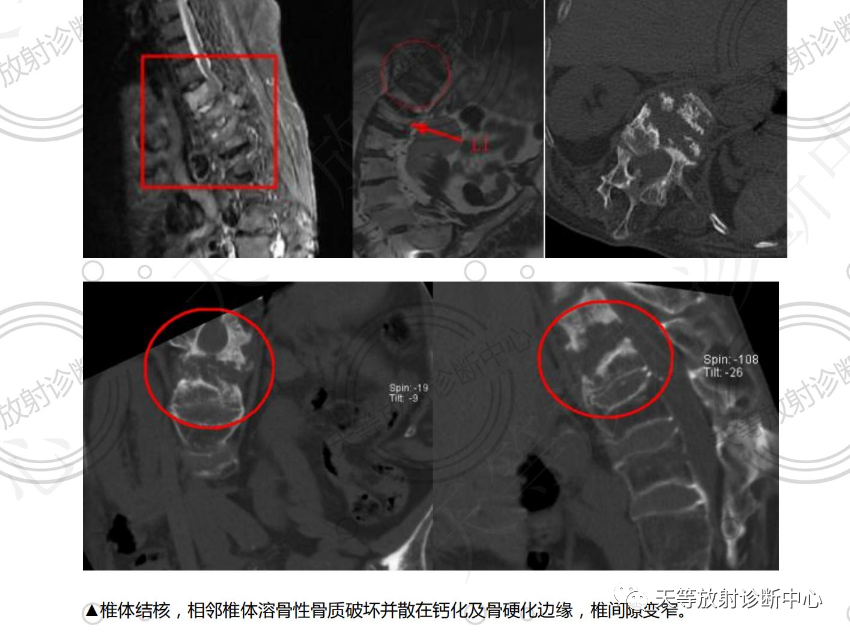

2、椎体结核:好发胸腰椎交界处,相邻椎体见溶骨性骨质破坏,伴周围软组织脓肿形成,破坏区见散在砂砾状钙化及硬化边,椎间隙变窄后凸畸形改变。病人常常患有肺结核相关病史。